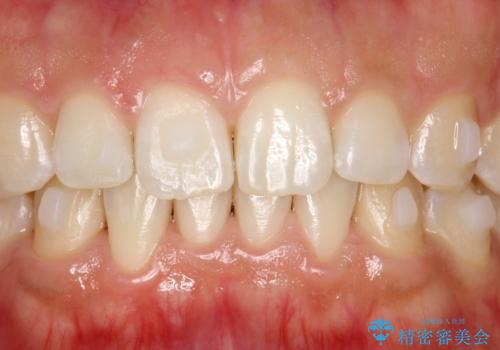

インビザライン中に歯の着色落としクリーニング PMTC

- インビザライン治療中に着色が気になるとのことでクリーニングを希望されました。PMTC30分コースを行いました。

インビザライン治療中には、歯の表面にアタッチメント(効率的に歯の移動をするもの)を設定します。そのため歯ブラシでは届きにくい細かい部分などに、歯石や着色がついてしまうことがあります。着色などを放置していると、着色なのか、虫歯なのかの判別もしずらく正確にお口の中の状態を診断できません。